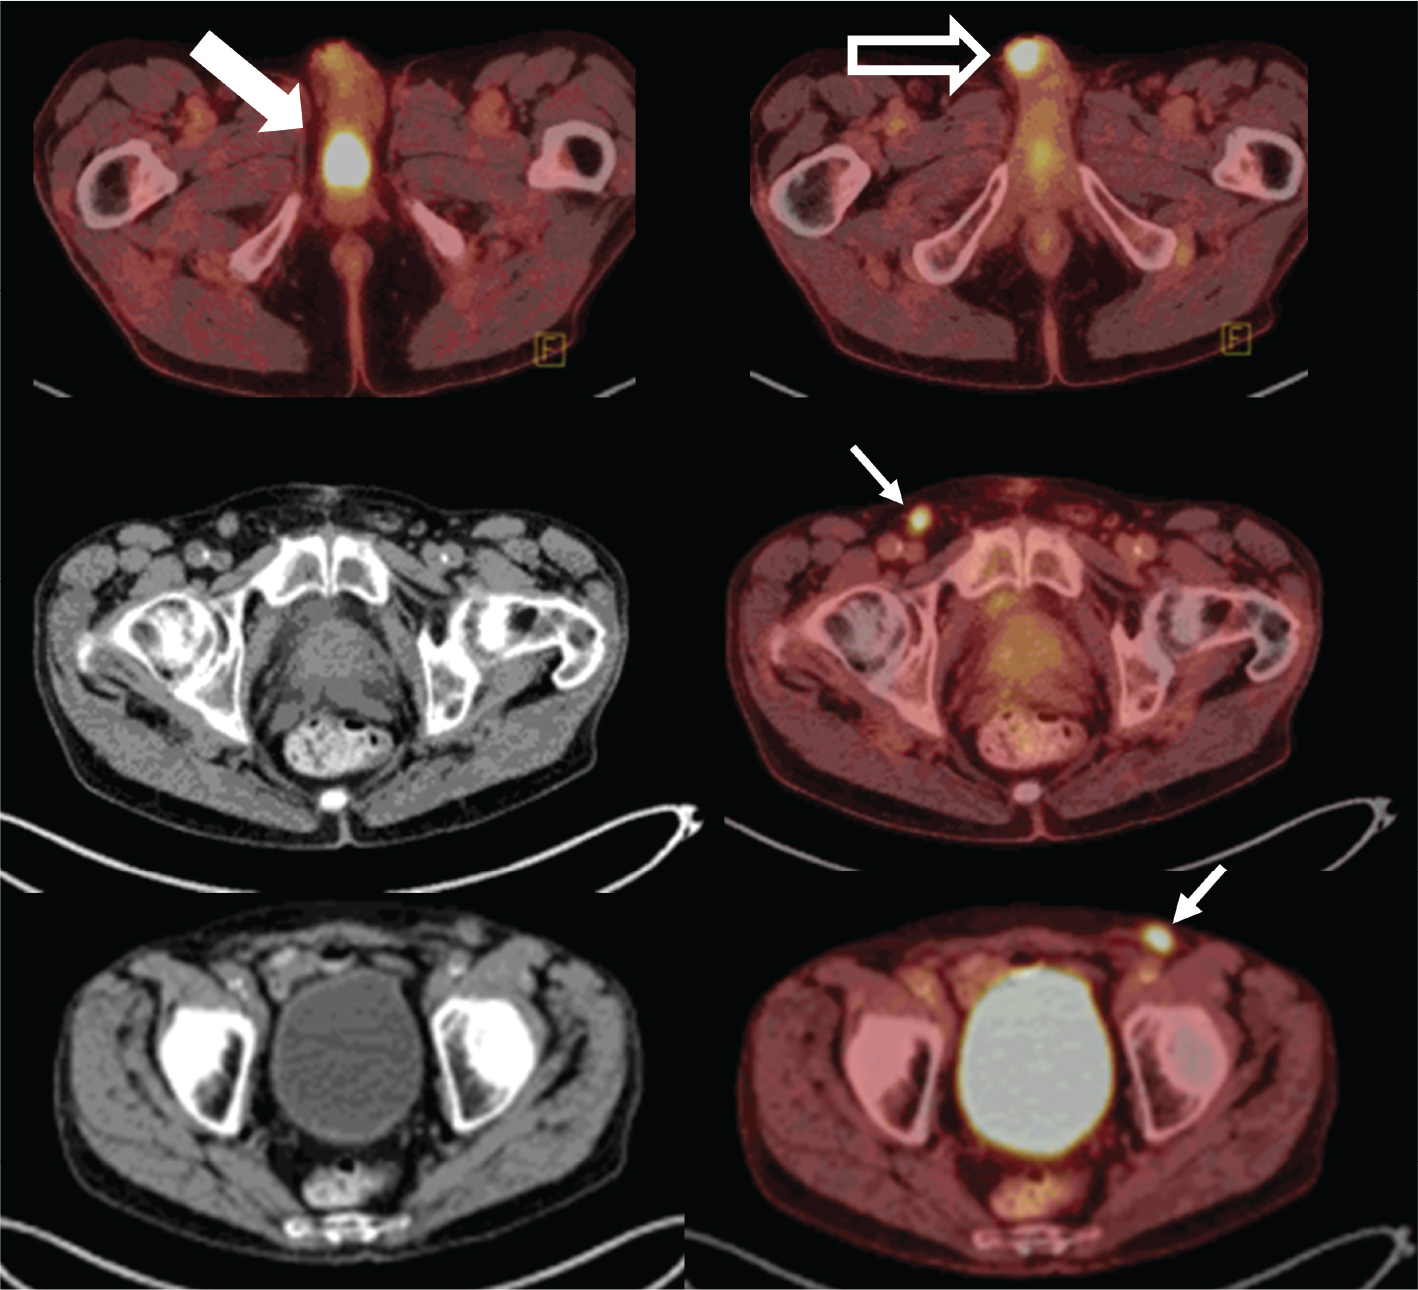

Fig 3

Figure 3. Seminal vesicles. FDG PET/CT demonstrates uptake within the bilateral seminal vesicles (thick solid arrows) in one patient (row 3A) and within an enlarged right seminal vesicle (thick solid arrow) in another patient (row 3B). Biopsy was negative in the first patient suggesting that activity likely represented urinary reflux of radiotracer (3A). Biopsy was positive for a plasmacytoma in the second patient (3B).

Involvement of the seminal vesicles is generally secondary. The most common neoplastic involvement of the seminal vesicles is direct extension of metastasis from prostate, bladder, or rectal cancer, often present upon the initial examination. Metastases from malignancies such as Merkel cell, lymphoma, and hepatocellular cancer have been seen. We present a documented case of plasmacytoma in a seminal vesicle (Figure 3B). Primary malignant neoplasms of the seminal vesicles are relatively rare: adenocarcinoma, sarcoma, leiomyosarcoma, and angiosarcoma are among those noted. A review of the literature showed only approximately 60 reported cases of adenocarcinoma of the seminal vesicles (1619). In the presence of an adjacent malignancy such as prostate cancer, direct extension should be considered. In other settings, metastatic disease or primary seminal vesicle cancer should be considered. As PET/CT findings are usually incidental, there are no established protocols/guidelines for PET/CT imaging of seminal vesicles.